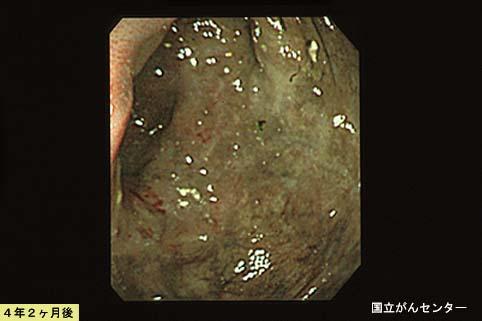

Progreso de la lesión con el paso del tiempo en el seguimiento de Colitis tipo venoesclerosante

Enfermedad Inflamatoria - Ulcerativa/Colitis venoesclerosante

colon/ascendente

Endoscopia

40 -